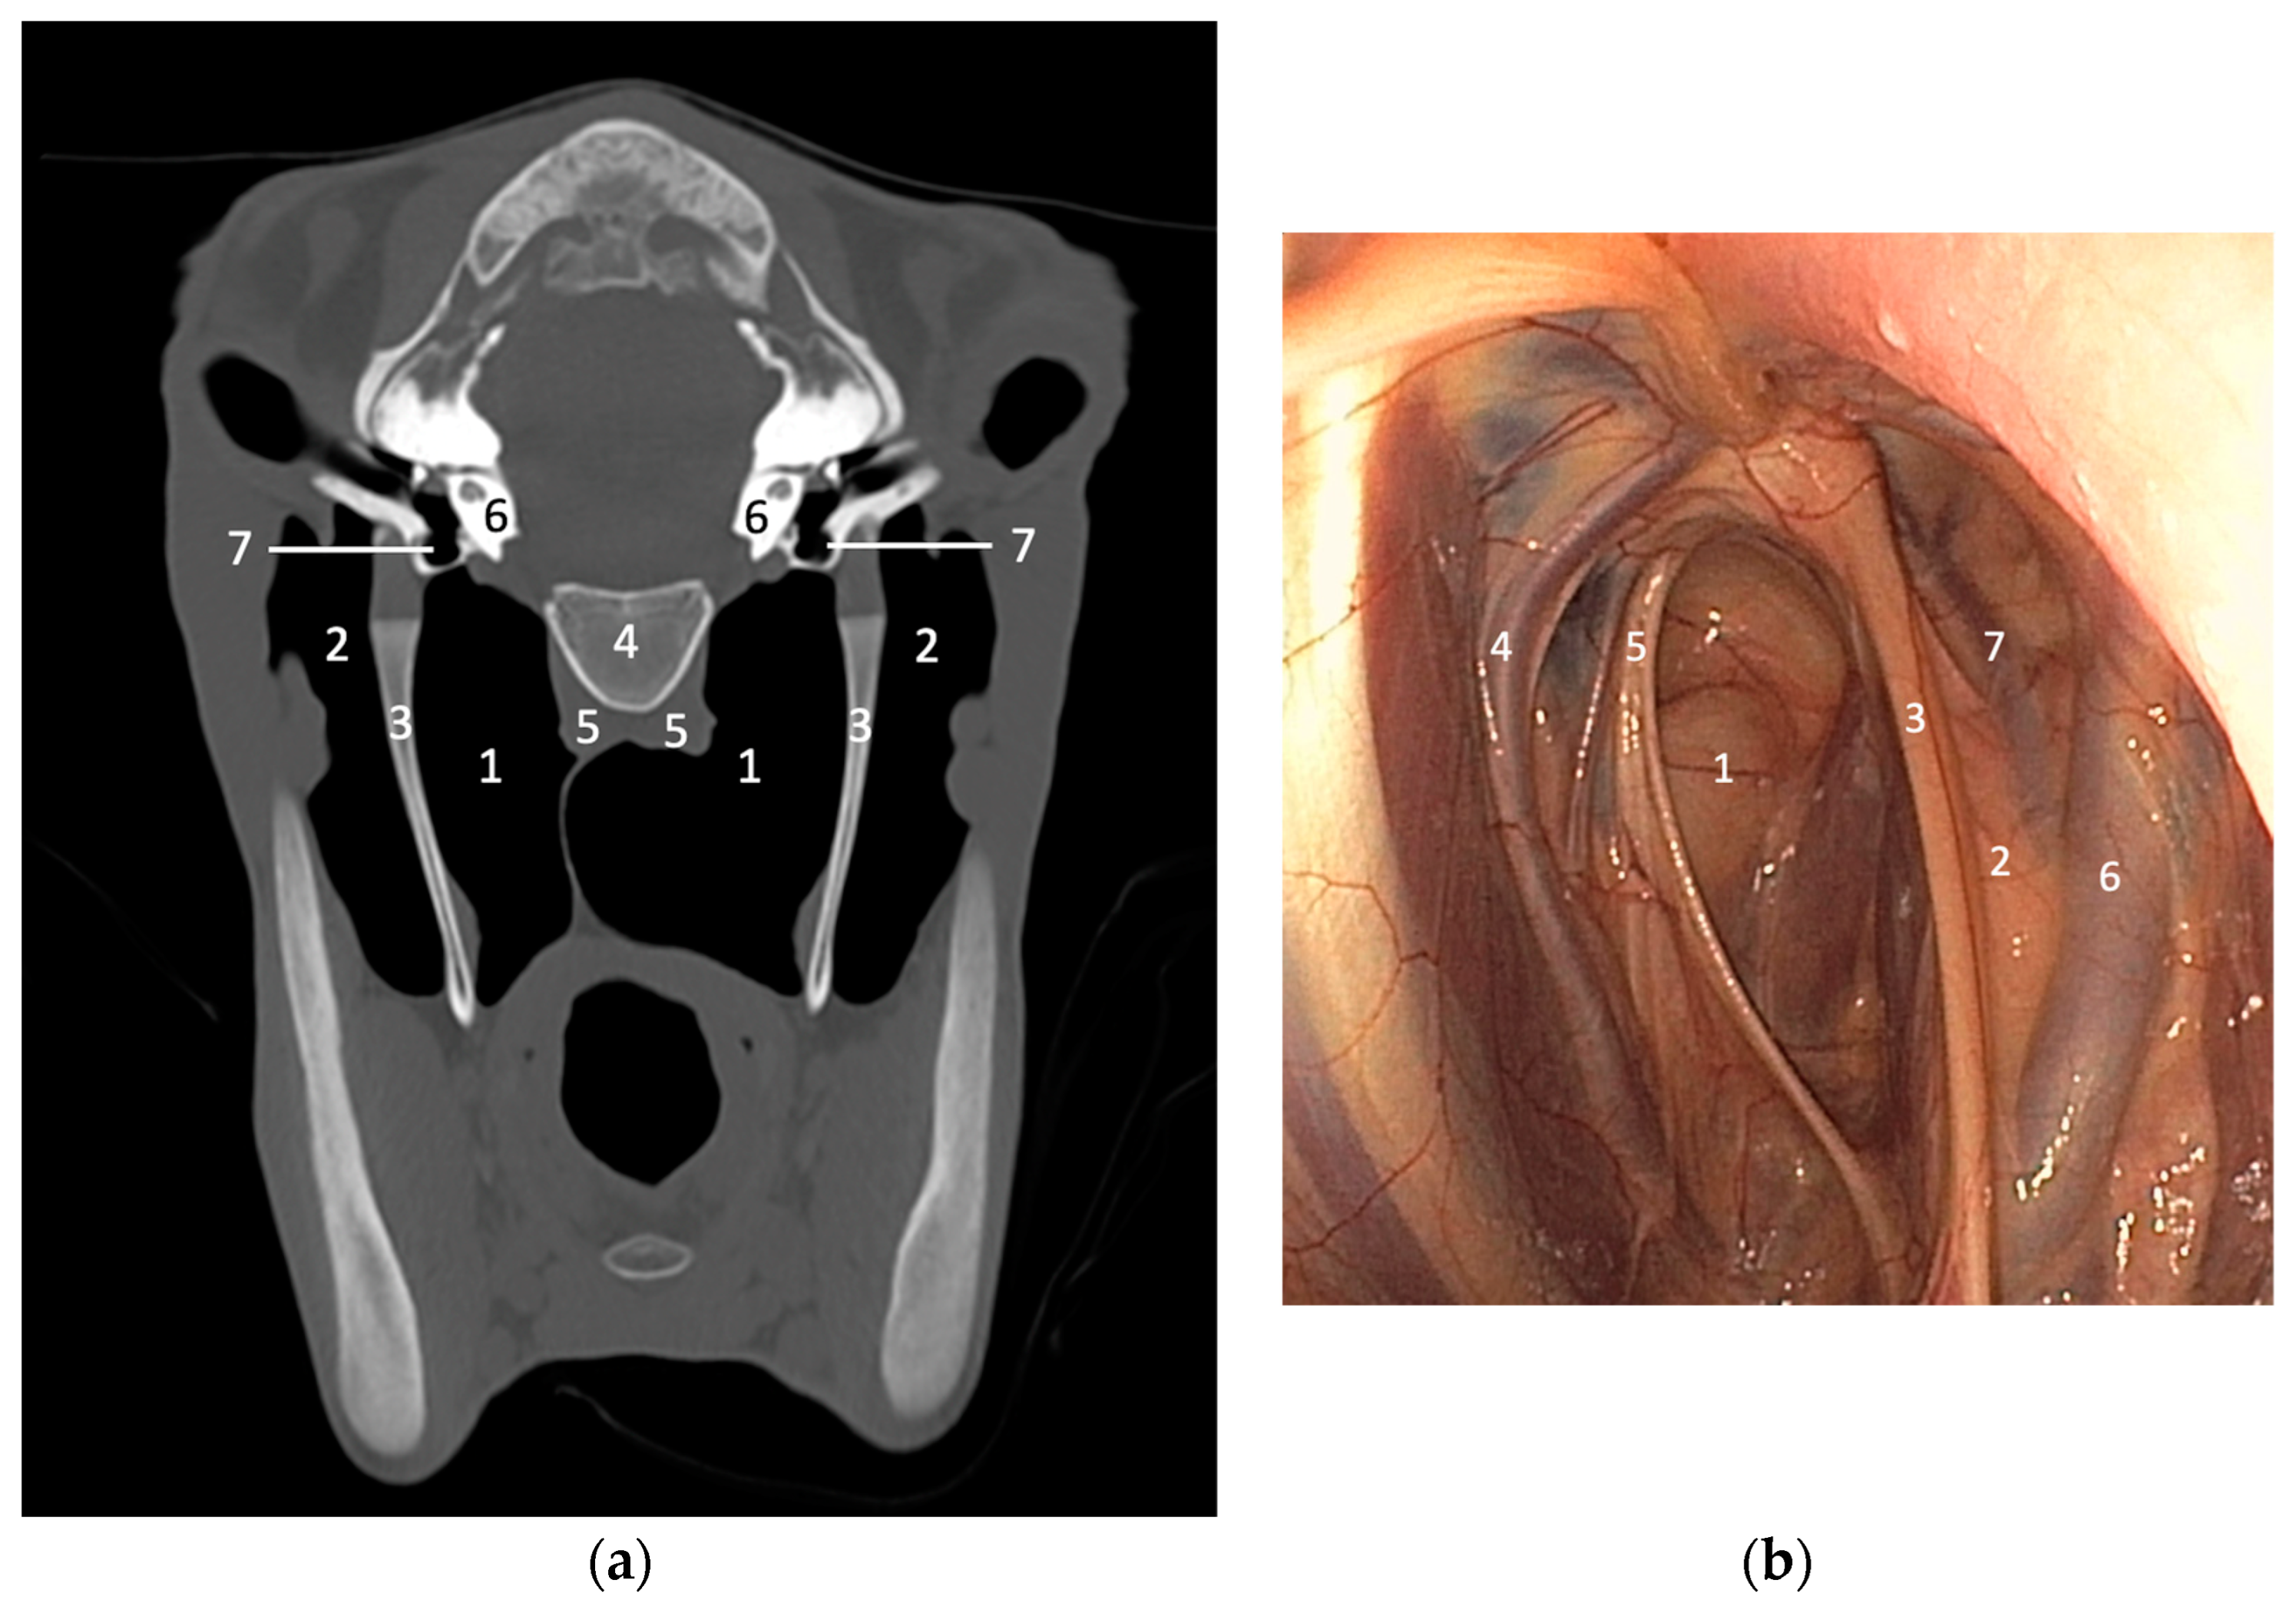

2. Use and Interest of the Different Imaging Techniques for Assessing the Guttural Pouches and Associated Structures

2.3. Cross-Sectional Imaging